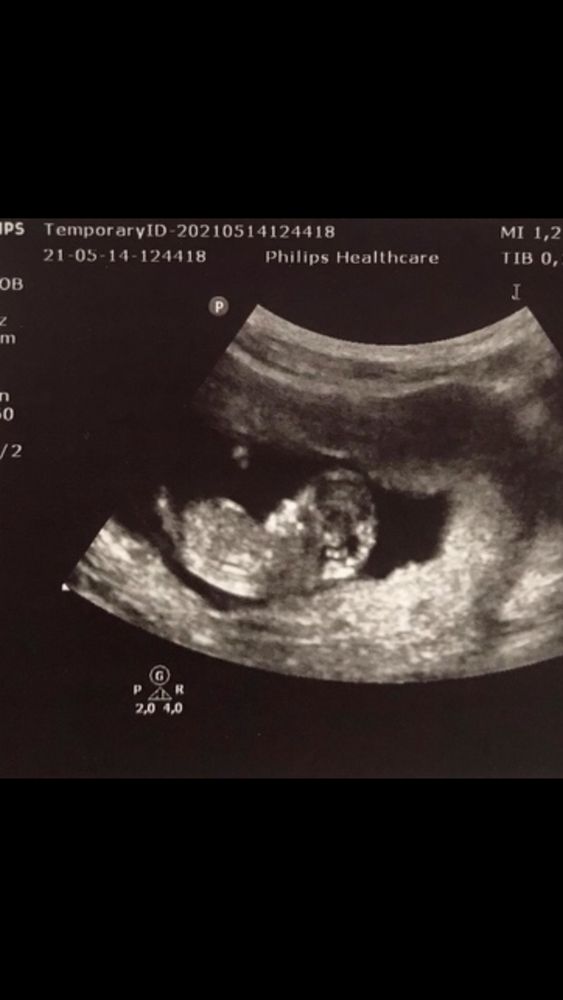

Это доченька на том же ровно сроке.

Дарина, не знаю, я думаю дело было в том, что срок реальный был меньше 11 недель. КТР малышки был 47 когда с ней был первый скрининг.